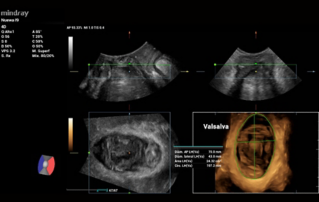

Female pelvic floor anatomy, which developed since the early 20th century, has had a variety of theories, including integral theory, three levels of vaginal support theory, "hammock hypothesis", and three-chamber system. Supporting structures such as pelvic floor muscles, fascia and ligament play an important role in maintaining the normal function of pelvic floor, among which levator ani muscle group is one of the most important supporting structures.